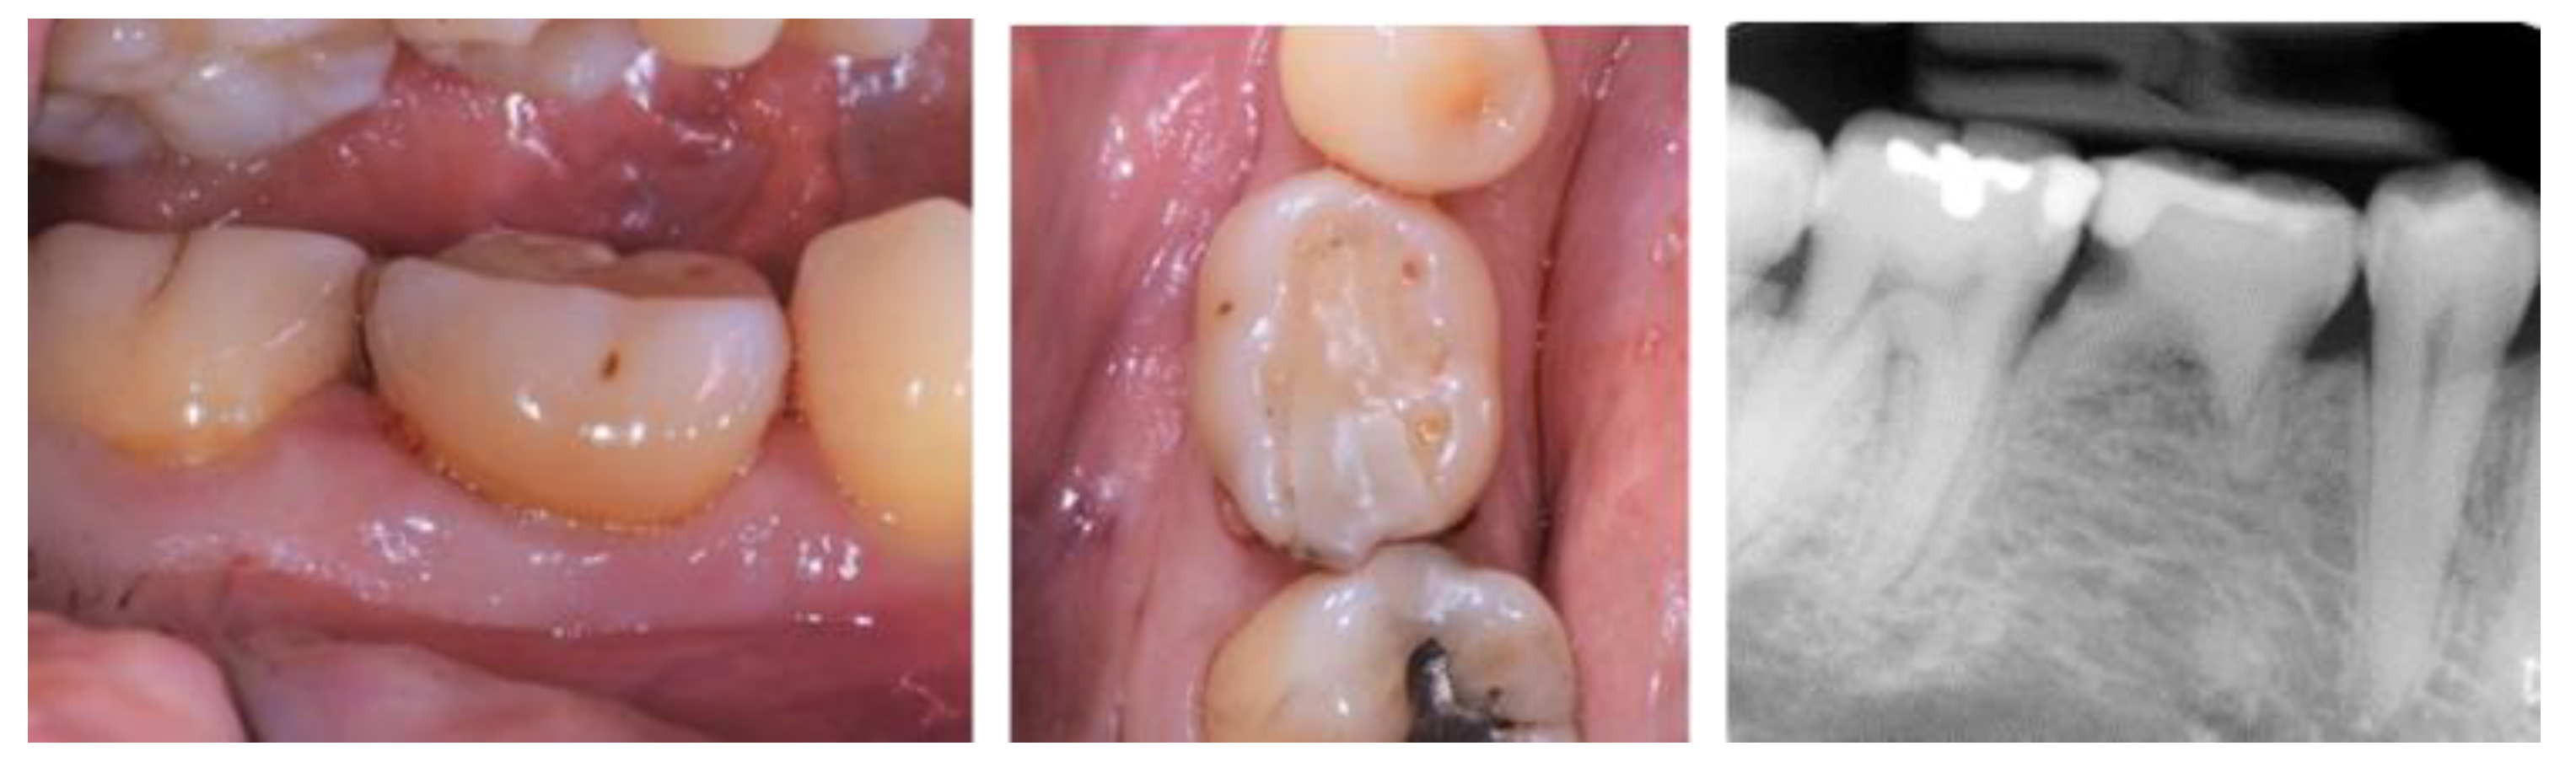

- Case 1:

- Case 2:

- Case 3:

- Case 4:

- Case 5: